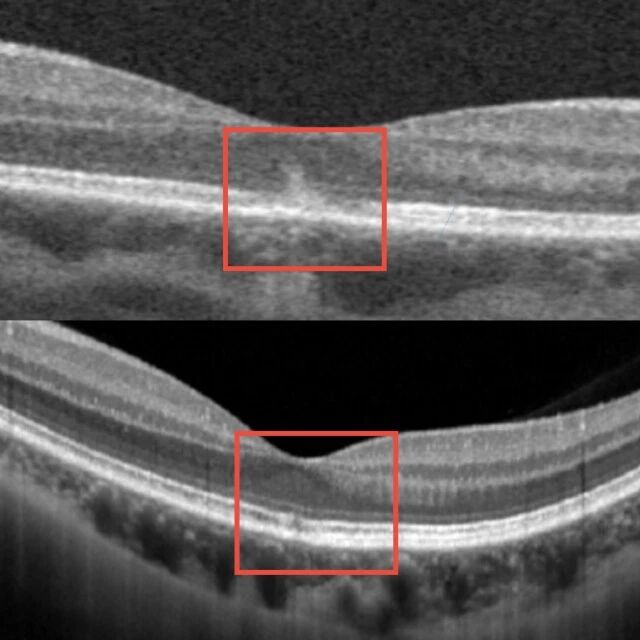

「生理状态下,墨镜或眼罩遮盖眼睛后,瞳孔会自动散大。一旦有强光射入,瞳孔就像一扇敞开的大门,来不及关上,造成人眼视网膜的黄斑部光损伤。」孙传宾说,经检查,患者的视网膜黄斑区出现暗红色斑点,被确诊为「黄斑热损伤」。

「黄斑是眼底最敏锐的感光组织,一旦受损,可能引发不可逆的视功能损害,甚至失明。」孙传宾解释,「幸运的是,患者的强光照射短暂,损伤较轻,经过积极的药物治疗,1 周后视力明显改善,1 个月后恢复正常。若光照强度更强或曝光时间更久,有可能造成不可逆的损伤,甚至致盲。」